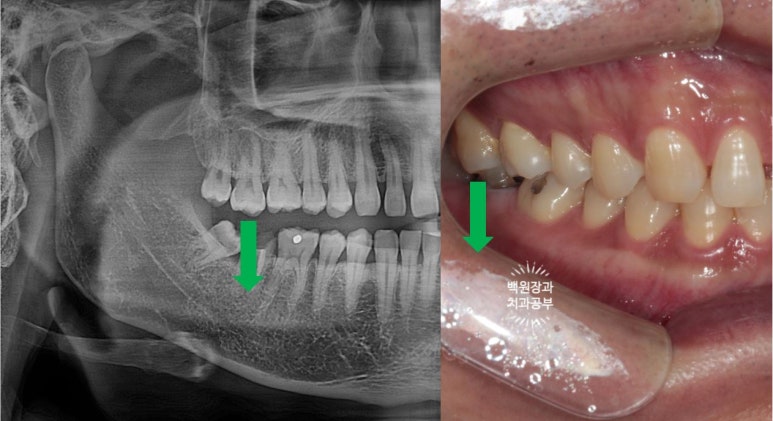

오른쪽 아래 두번째 큰어금니가 뿌리만 남아있은지가 너무 오래되서, 그 공간으로 짝꿍 치아인 (대합치) 오른쪽 위 두번째 큰어금니가 꽤나 내려와 있었어요.

치과에서는 치아가 정출(extrusion)되었다고 표현합니다.

공간이 침범되어 있는 상태였기 때문에 선택을 해야하는 상황이었답니다.

비슷한 케이스의 다른 환자분의 경우인데,

왼쪽 위 어금니 부위 임플란트 수술을 위해 정출되어 있는 왼쪽 아래 두번째 큰 어금니를 의도적 신경치료 (근관치료) 후 크라운으로 씌워 준 경우입니다.